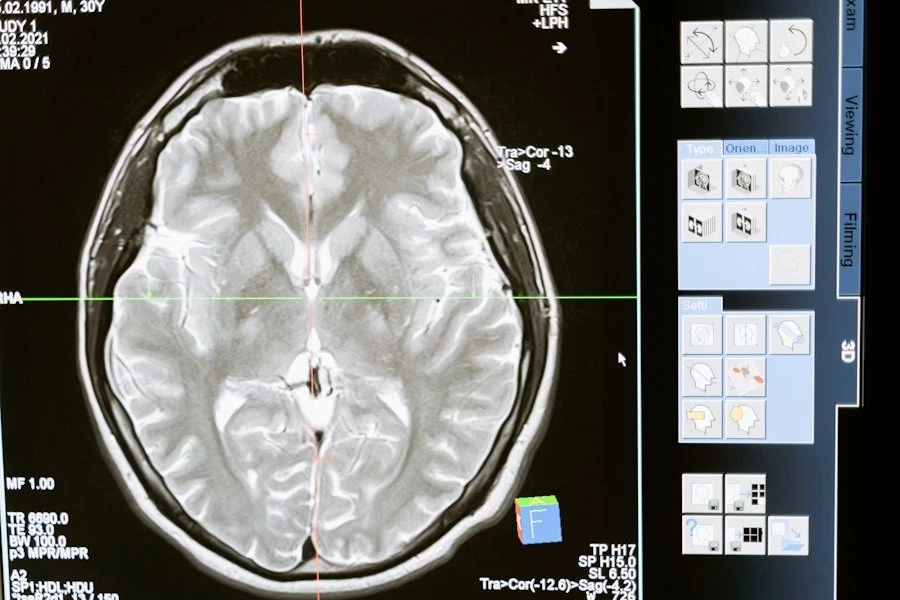

Нейробиологи РФ работают над созданием нейроинтерфейса, помогающем улучшить реакции у пожилых людей. Их исследования основаны на использовании транскраниальной магнитной стимуляции, или ТМС, сообщает ТАСС.

ТМС — это метод, при котором магнитные поля воздействуют на активные участки мозга. Этот метод может быть полезен в реабилитации после травм двигательного аппарата. Нейробиологи утверждают, что ТМС способствует активизации мозговой деятельности.

В ходе экспериментов исследователи усложнили задачу и использовали разные изображения кубиков. Направление граней определялось по их толщине. Согласно данным электроэнцефалограммы (ЭЭГ), магнитная стимуляция активных участков мозга привела к ускорению выполнения задач на 20%. Этот эффект продолжал сохраняться в течение полутора часов.